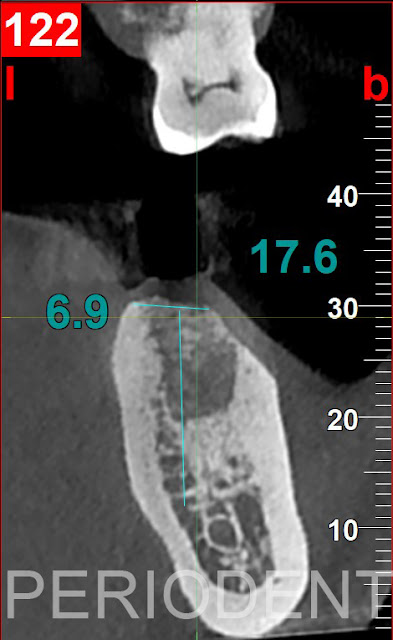

15. 術後九個月時,口掃取模及電腦斷層檢查製作數位植牙手術導版

16. 拔牙補骨術後一年時植牙